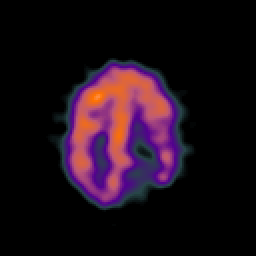

SPECT TC Study #7 -- Slice #41

[Home][Help][Clinical][Tour 1][Tour 2][Tour 3] Slice 41